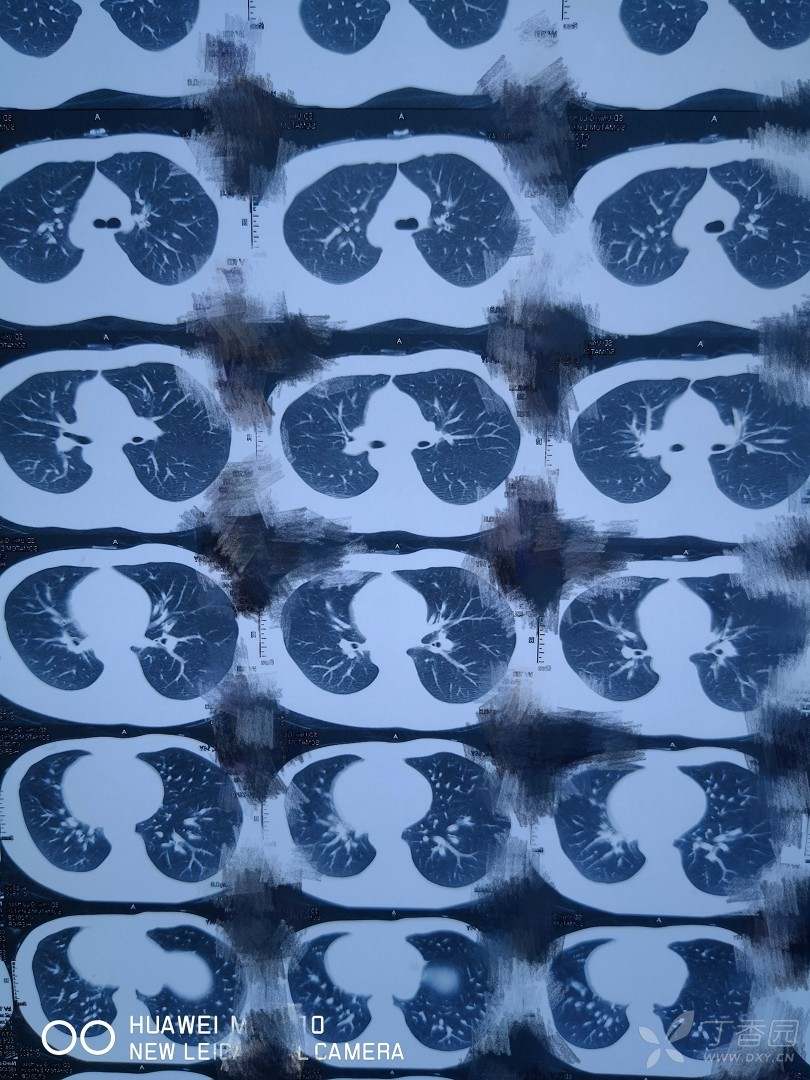

服毒后第七天的ct,未见明显纤维化。

最新检查结果。双肺可见少量纤维灶。